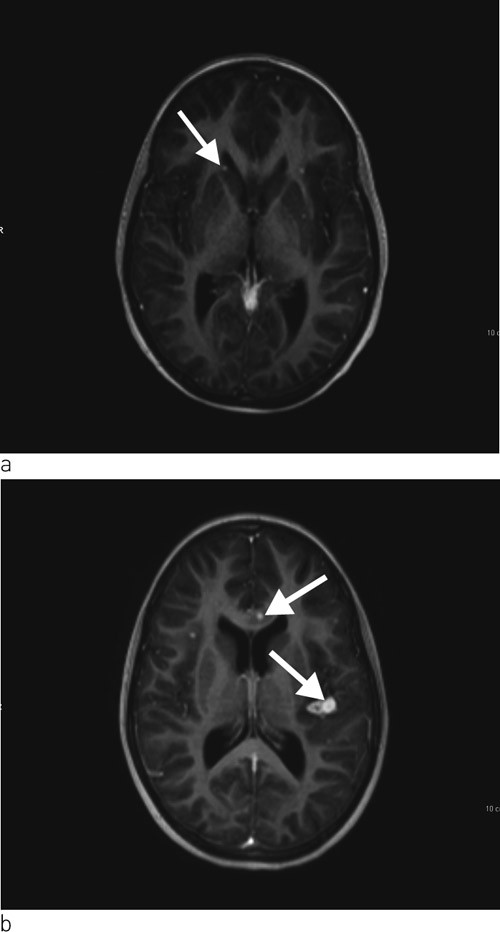

Ei veke etter innlegging var jenta klinisk dårlegare. Ho var kvalm og hadde svært redusert matlyst. Vi starta difor med intravenøs væsketilførsel og ernæring. Det vart tatt indusert sputum og gastrisk aspirat til direkte mikroskopi, PCR og dyrking med tanke på Mycobacterium tuberculosis. Vi rekvirerte også ein Quantiferon-TB Gold test. Dagen etter vart ho spinalpunktert, og vi fann leukocyttar 444 · 10⁶/l (< 3,0 · 10⁶/l), 80 % polynukleære og 20 % mononukleære, glukose 3,2 mmol/l og protein 0,31 g/l (< 0,50 g/l). På mistanke om miliær tuberkulose med meningitt starta vi med standard antituberkuløs behandling med isoniazid, rifampicin, pyrazinamid og etambutol samt pyridoksin. Dagen etter vart det i tillegg starta med intravenøs cefotaksimbehandling. Tre dagar seinare vart det gjort MR av cerebrum, som viste multiple små kontrastladande lesjonar i hjerneparenkymet, dei fleste i overgangen mellom grå og kvit substans, og i tillegg ein lesjon i basalgangliene på venstre side (fig 3a). Det var minst 16 lesjonar supratentorialt og tre infratentorialt, og den største målte 5 mm i diameter. Det vart gjort ekkokardiografi som viste normale forhold. Det vart ikkje påvist antistoff mot humant immunsviktvirus (hiv).

På grunn av usikker diagnose og komplisert sjukdom vart barnet dagen etter MR-undersøkinga overført til eit anna universitetssjukehus. Vi fekk så svar på Quantiferon-TB Gold som var 5,17 IU/ml (< 0,35 IU/ml). Augelege fann at jenta hadde korioretinale infiltrat bilateralt. MR av abdomen med kontrast viste hepatosplenomegali utan fokal patologi samt forstørra lymfeknutar i leverhilus og paraaortalt. 13 dagar etter overføring kom det melding om positiv polymerasekjedereaksjonstest (PCR) for M tuberculosis-komplekset i indusert sputum. Ei veke seinare vart det stadfesta vekst av M tuberculosis i indusert sputum og i spinalvæske. Stammen var sensitiv for alle testa medikament. Etter 14 dagar vart jenta overført til lokalsjukehuset. Røntgen av thorax etter to månaders behandling viste markert tilbakegang av lungefortettingane. Samstundes vart det tatt ein kontroll-MR av cerebrum som viste at dei intracerebrale lesjonane hadde auka i storleik og at det var fleire nytilkomne lesjonar (fig 3b). Jenta var framleis innlagt i avdelinga. Ho hadde ingen nyoppståtte nevrologiske symptom eller utfall. Visuelt framkalte potensial (VEP), som er ein spesifikk test av nervus opticus, vart undersøkt tidleg i behandlingsforløpet og etter åtte veker. Funna ved desse undersøkingane var normale.

Ved kliniske kontrollar to, åtte og tolv månader etter utskriving var det tilfredsstillande forhold. MR av cerebrum etter sju månader med behandling viste nær komplett tilbakegang av alle lesjonar. Dei korioretinale infiltrata gjekk også fullstendig tilbake. Lymfocyttpopulasjonar vart kontrollert på same tidspunkt og viste no tilnærma normale verdiar.